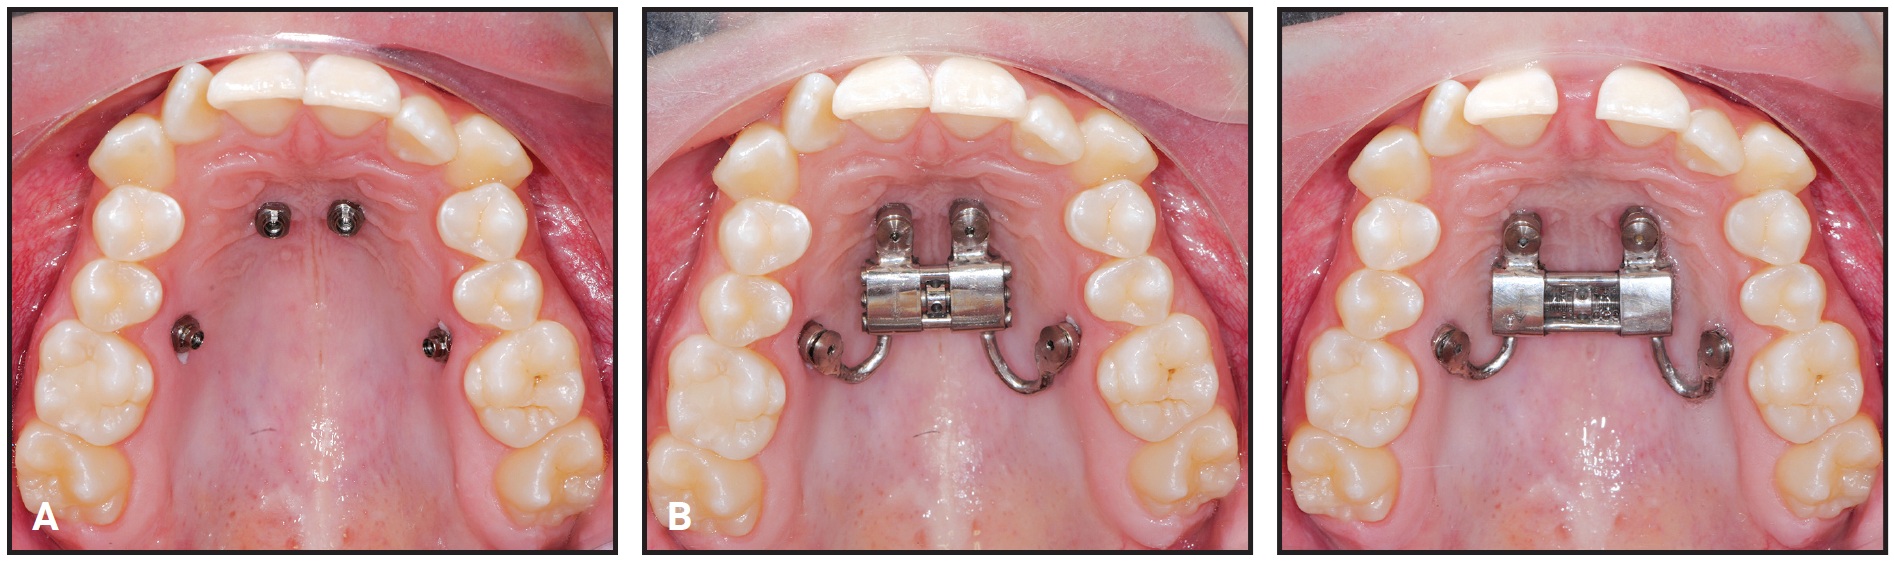

Analysis of the CBCT image indicated sufficient bone for two 9mm × 2mm mini-implants† in the anterior palate lateral to the suture. Because the posterior paramedian bone was insufficient for skeletal anchorage, we decided to place two 7mm × 2mm mini-implants in the alveolar ridge between the roots of the second premolars and first molars. After overlaying the virtual model and the CBCT, the positions of the anterior and posterior mini-implants were digitally planned. The insertion guides were digitally produced (Fig. 3), and the mini-implants and Quadexpander were inserted at the same appointment (Fig. 4A,B).

Fig. 4 Case 1. A. Quadexpander on model. B. Insertion of TADs. C. Before and after 30 days of expansion.

The patient was instructed to turn the expander .2mm per day, resulting in about 6.5mm of boneborne expansion after 30 days (Fig. 4C).